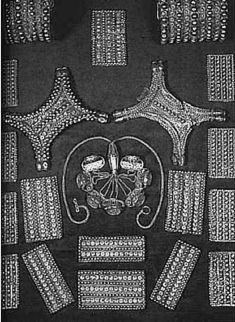

Камень из Ики с изображением операции

И все-таки сильнее всего поражает воображение наших современников серия камней, также найденных доктором Кабрерой, которые можно рассматривать как своеобразный учебник или же «отчет» об операции по пересадке сердца. На одном из камней искусно выгравирован молодой человек, которому жрец (или врач?) вскрывает грудную клетку. Второй врач, стоящий рядом, держит в руках набор инструментов. Изображение на следующем камне – сердце, только что извлеченное из груди донора. На третьем камне – старец (о его возрасте говорят многочисленные морщины на лице), из груди которого вынимают больное сердце, а вместо него помещают здоровое, взятое у юноши. Следующий сюжет – прооперированный старик с только что зашитым швом. В его гортань введена трубка, соединенная со своеобразным насосом – аппаратом искусственного дыхания! На других каменных глыбах можно рассмотреть весь послеоперационный период: прооперированный человек постепенно начинает дышать самостоятельно; хирург прослушивает его сердце; вполне здоровый старец делает первые самостоятельные шаги. Интересна еще одна картинка: для того чтобы после изъятия больного сердца старик не умер, к его кровеносной системе подключают сердце лежащей рядом женщины. Именно оно и поддерживает жизнь старика во время всей операции по трансплантации.

Ни для кого не секрет, что делать подобные операции могли только люди или же какие-то другие существа, в совершенстве знавшие анатомию и физиологию, знавшие о том, что пересаженные органы могут отторгаться организмом реципиента, и умевшие бороться с этим. Кроме того, они должны были уметь проводить реанимационные мероприятия, а также знать правила асептики и антисептики, иначе пациент погиб бы в послеоперационный период от заражения крови. Да и инструменты древних хирургов должны были быть не менее совершенными, чем современные.

Наконец, кем же были доисторические реципиент и донор? На теле юноши нет следов от ран, то есть он не погиб в бою, а был положен на операционный стол в полном здравии. Вряд ли он пошел на такую жертву добровольно. Значит, в обществе, владеющем уникальными научными знаниями, были бесправные существа, рабы, жизнь которых ничего не стоила?